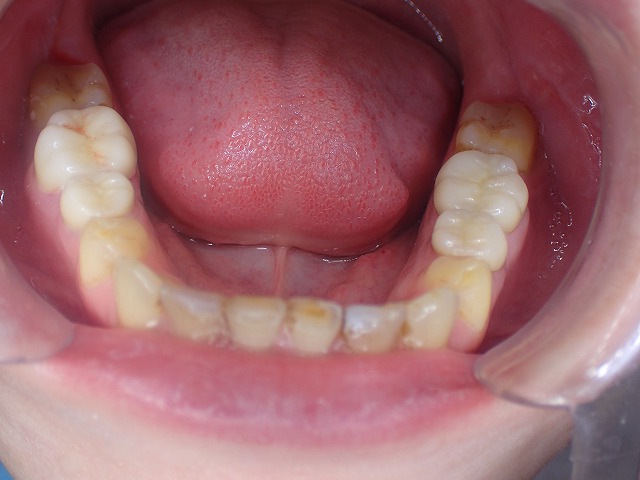

両側の摩耗したCAD/CAM冠を

ジルコニアクラウンに交換できました。

矯正後 過蓋咬合と歯ぎしり もう少し矯正で補正してくれれば

過蓋咬合も歯列矯正で補正できたはず 決して失敗ではないが

過蓋咬合ですので、下の歯に上の歯がかぶさり

下の歯が見えません。